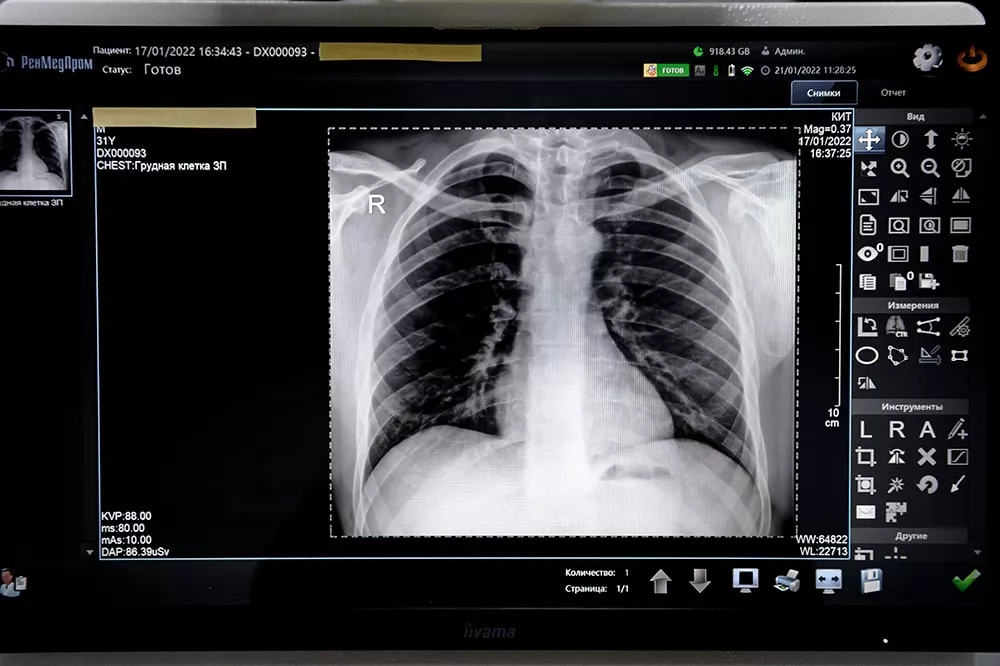

Рентгенография – это популярный метод диагностики, открытый немецким физиком Вильгельмом Рентгеном в 1895 году. Метод основан на уникальном свойстве электромагнитных волн проникать сквозь органы и ткани человека. Просвечивая тело, рентгеновские лучи теряют свою интенсивность. Степень их ослабления зависит от плотности и структуры ткани, через которую они проходят. Это позволяет получить на фотопластине различные изображения, оценить состояние костной ткани, внутренних органов, определить наличие в организме новообразований и посторонних предметов.

- рентген лёгких

- болезни органов дыхания

В зависимости от области исследования рентген может проводиться в положении стоя, сидя или лёжа. Врач-рентгенолог находится в соседнем помещении, откуда он управляет аппаратом и наблюдает за пациентом. Чтобы изображение получилось максимально чётким, в момент выполнения снимка нельзя двигаться, поэтому специалист просит пациента задержать на несколько секунд дыхание. Вся процедура занимает от 5 до 15 минут.

Запись результатов рентгенологического исследования предоставляется на диске. Напечатанный снимок оплачивается отдельно.